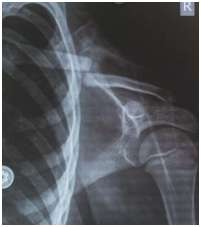

骨折移位明显的

儿童最适合弹性髓内钉治疗